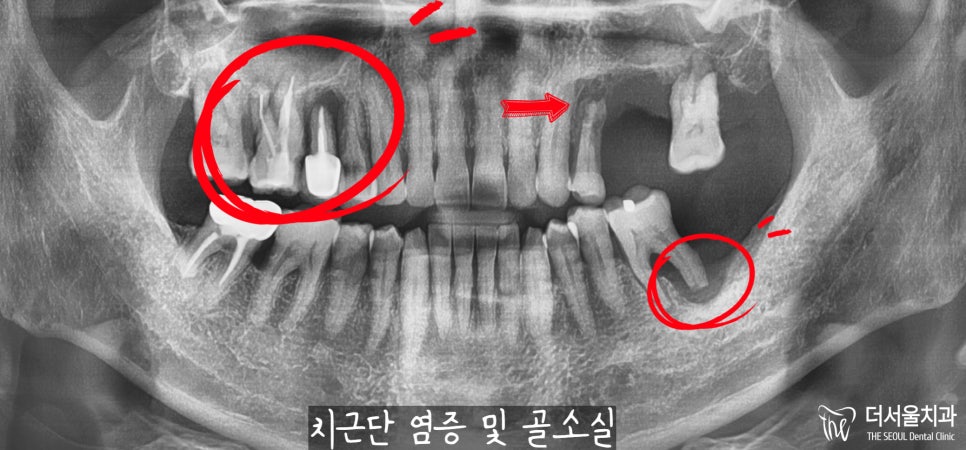

더 정확한 진단을 내릴 수 있도록

태평동 치과 에서는

파노라마(X-Ray) 촬영에 들어갔습니다.

예측했던 것보다

더 상황은 좋지 않았습니다.

우선 10번대를 살펴보면 치근단 염증으로

뿌리 끝에 거멓게 변해있는 것을

볼 수 있으실텐데요.

이미 골소실이 많이 일어났고,

그 영향으로 이가 흔들릴 수밖에 없었습니다.

20번대 또한 마찬가지로

심하게 뼈를 잃게 되었으며,

그 영향으로 치아 흔들림이

나타날 수밖에 없었습니다.

30번대 어금니 또한 마찬가지,

뿌리 끝에 염증이 심하여

뼈가 사라져 치아 흔들림이